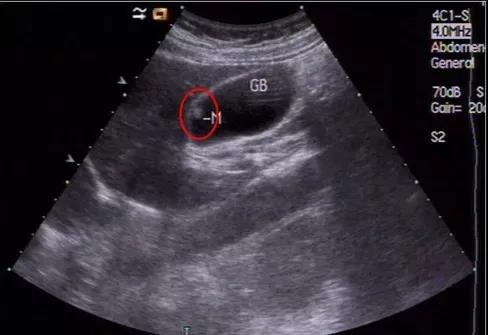

①看真假:真正可能變癌的是真息肉,假息肉不用管;

②看大小:長(zhǎng)到1厘米了就需要考慮手術(shù),風(fēng)險(xiǎn)大了;